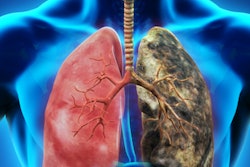

Dr. Chambers assisted in the world's first heart transplant, which was performed in Cape Town, South Africa, in 1967 by surgeon Dr. Christiaan Barnard, and she worked in three continents in cardiac and thoracic radiology, noted the Bucks Free Press.